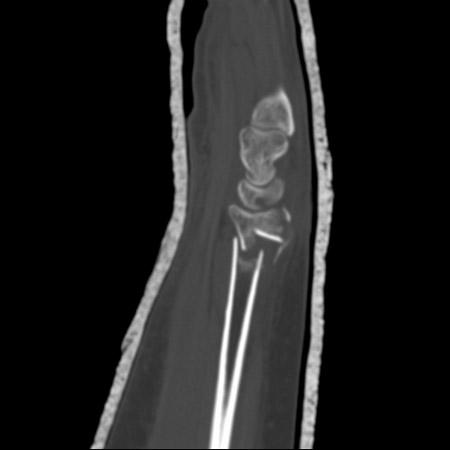

Em pacientes em que a fixação cirúrgica é considerada, uma TC do rádio distal é útil para a análise da geometria da fratura extra e intra-articular e para o planejamento pré-operatório.[30]

Uma TC também pode evidenciar quaisquer fraturas ocultas ao redor do carpo.[Figure caption and citation for the preceding image starts]: As tomografias computadorizadas (TCs) do punho fornecem detalhes excelentes para avaliação da geometria da fratura, do comprometimento articular e do grau de cominuiçãoDo acervo do Dr. Chaitanya S. Mudgal [Citation ends].

fratura do rádio distal ou da ulna, com esclarecimento da extensão da cominuição e/ou do comprometimento articular